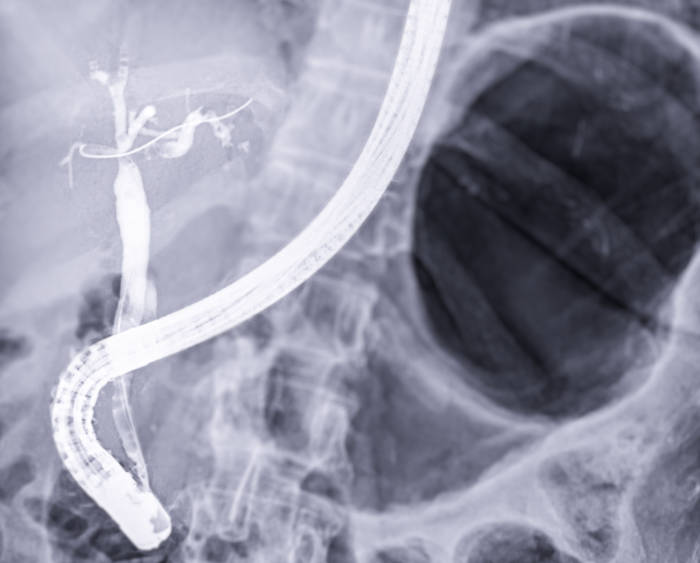

Die endoskopisch retrograde Cholangiopankreatikographie (ERCP) kombiniert Endoskopie mit Röntgendiagnostik und ermöglicht es, die feinen Gänge der Gallenblase und Bauchspeicheldrüse sowohl zu untersuchen als auch zu behandeln.

So funktioniert die ERCP: Über ein spezielles Endoskop (Duodenoskop) führen wir einen sehr dünnen Katheter durch den natürlichen Zugang – die Papille im Zwölffingerdarm – in die Gallen- oder Bauchspeicheldrüsengänge ein. Durch Kontrastmittel werden die Gänge unter Röntgenkontrolle sichtbar gemacht. Das Besondere: Wir können nicht nur schauen, sondern auch sofort behandeln.

Dieses minimal-invasive Verfahren kann in vielen Fällen größere chirurgische Eingriffe am Bauch ersetzen und ermöglicht eine schonendere Behandlung mit schnellerer Erholung.

Wir führen ambulante Folge-ERCPs durch – beispielsweise nach stationärer Erstbehandlung, wenn erneute Stentwechsel, eine Stententfernung oder weitere Interventionen wie wiederholte Steinentfernungen notwendig sind. Dies erspart Ihnen einen stationären Aufenthalt.

Entsprechend den Empfehlungen der Fachgesellschaft DGVS (Deutsche Gesellschaft für Gastroenterologie, Verdauungs- und Stoffwechselkrankheiten) halten wir uns konsequent an die Leitlinien zur sektorenübergreifenden Erbringung gastroenterologischer Endoskopie, wonach Erst-ERCPs eine stationäre Nachüberwachung erfordern.

Zur Gewährleistung höchster Patientensicherheit führen wir daher ausschließlich ambulante Folge-ERCPs durch – und das auf Basis unserer umfassenden Expertise aus jahrelanger universitärer Tätigkeit mit einem großen Volumen komplexer ERCP-Eingriffe. Diese langjährige Hochvolumen-Erfahrung ermöglicht es uns, auch anspruchsvolle Folgeeingriffe sicher und erfolgreich ambulant durchzuführen.